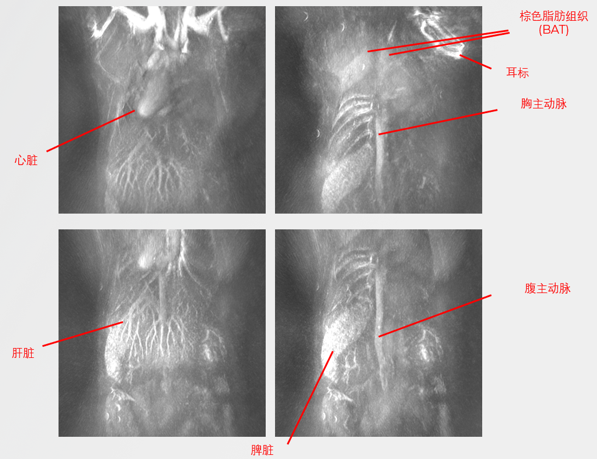

无标记小鼠血管成像